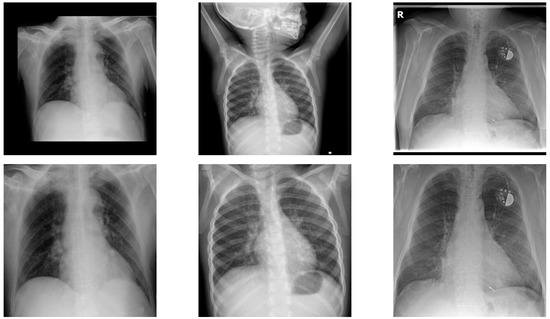

The recent Coronavirus Disease 2019 (COVID-19) pandemic has put a tremendous burden on global health systems. Medical practitioners are under great pressure for reliable screening of suspected cases employing adjunct diagnostic tools to standard point-of-care testing methodology. Chest X-rays (CXRs) are appearing as [...] Read more.

The recent Coronavirus Disease 2019 (COVID-19) pandemic has put a tremendous burden on global health systems. Medical practitioners are under great pressure for reliable screening of suspected cases employing adjunct diagnostic tools to standard point-of-care testing methodology. Chest X-rays (CXRs) are appearing as a prospective diagnostic tool with easy-to-acquire, low-cost and less cross-contamination risk features. Artificial intelligence (AI)-attributed CXR evaluation has shown great potential for distinguishing COVID-19-induced pneumonia from other associated clinical instances. However, one of the associated challenges with diagnostic imaging-based modeling is incorrect feature attribution, which leads the model to learn misguiding disease patterns, causing wrong predictions. Here, we demonstrate an effective deep learning-based methodology to mitigate the problem, thereby allowing the classification algorithm to learn from relevant features. The proposed deep-learning framework consists of an ensemble of convolutional neural network (CNN) models focusing on both global and local pathological features from CXR lung images, while the latter is extracted using a multi-instance learning scheme and a local attention mechanism. An inspection of a series of backbone CNN models using global and local features, and an ensemble of both features, trained from high-quality CXR images of 1311 patients, further augmented for achieving the symmetry in class distribution, to localize lung pathological features followed by the classification of COVID-19 and other related pneumonia, shows that a DenseNet161 architecture outperforms all other models, as evaluated on an independent test set of 159 patients with confirmed cases. Specifically, an ensemble of DenseNet161 models with global and local attention-based features achieve an average balanced accuracy of 91.2%, average precision of 92.4%, and F1-score of 91.9% in a multi-label classification framework comprising COVID-19, pneumonia, and control classes. The DenseNet161 ensembles were also found to be statistically significant from all other models in a comprehensive statistical analysis. The current study demonstrated that the proposed deep learning-based algorithm can accurately identify the COVID-19-related pneumonia in CXR images, along with differentiating non-COVID-19-associated pneumonia with high specificity, by effectively alleviating the incorrect feature attribution problem, and exploiting an enhanced feature descriptor. Full article